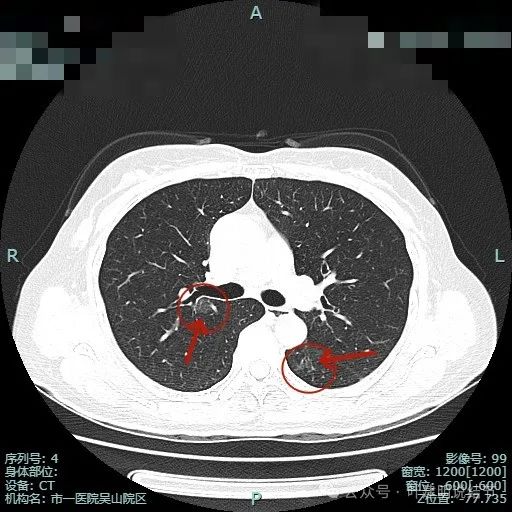

出现小空泡征以及偏实性成分,并有淡磨玻璃成分,整体轮廓较清,瘤肺边界较为清楚。

叶间胸膜有牵拉,病灶内部密度欠均匀。表面有浅分叶征。

病灶1密度已经淡了;病灶2刚好位于上叶支气管发现后段支气管处,与支气管壁没显著间隙。

病灶1已经淡,且靠降主动脉近;病灶2密度其实也不纯,灶内有微小血管穿行,边缘侧有血管贴边,与支气管管壁间没有间隙。